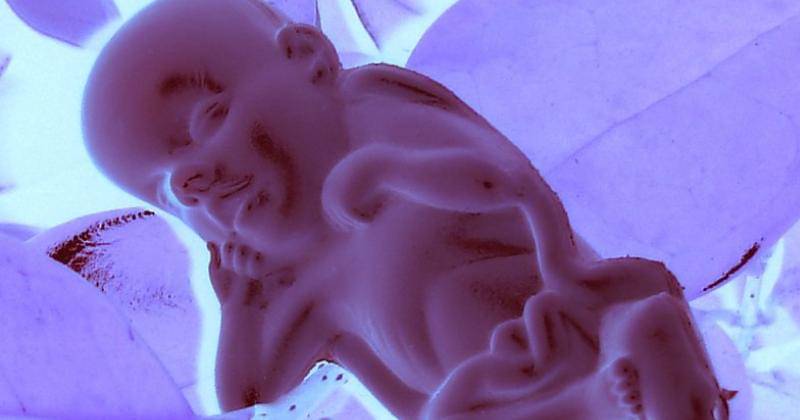

2. Anggota tubuh mulai terbentuk

Pada usia kehamilan dua bulan ini, anggota tubuh janin satu persatu sudah mulai terbentuk secara perlahan.

Tampilan wajah sudah mulai terbentuk, mata, telinga, rahang, dan hidung sudah berada di posisi yang sesuai. Kemudian tangan janin akan mengepal disertai jari-jari yang ada di kepalan tersebut.

Selain itu, kaki, tungkai, dan jari-jari kaki juga akan segera tumbuh dan berkembang. Begitu juga dengan tabung saraf yang berisi otak dan sumsum tulang belakang yang sudah terbentuk.